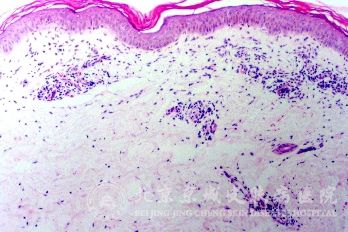

北京京城皮肤医院指出,药物皮炎的发病机制:非变态反应,可能与药物毒性作用或光敏感作用有关。如药物剥脱性皮炎,是由于药物用量过大或服用时间过长所致的毒性反应;服用磺胺药后,若暴露于阳光下,由于光敏感作用就可能发生皮炎。